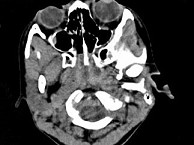

4.女,8岁,头痛,鼻塞半年余,CT如图所示,最可能诊断为 ( )![]() ![]() ![]() ![]() |

| 正确答案:C |